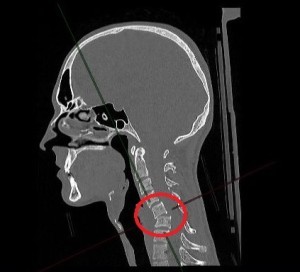

Проведенное обследование с помощью УЗИ, томографии всего тела и МРТ выявило множественные переломы шейных позвонков, вывих одного из них, разрыв межпозвонкового диска с образованием грыжи, сдавившей спинной мозг. По словам врача-нейрохирурга, кандидата медицинских наук Петра Галкина, ситуация с развитием отека спинного мозга грозила пациенту в лучшем случае параличом, а в худшем — гибелью, поэтому решение о проведении операции было принято быстро, и о консервативном лечении не могло быть и речи.

Операцию проводили хирурги Петр Галкин и Михаил Ветров. Под увеличением, с использованием операционного микроскопа, через небольшой разрез кожи по передне-боковой поверхности шеи была удалена травматическая грыжа диска. Затем под рентген-контролем был успешно вправлен вывих, а позвонки зафиксированы при помощи титановой пластины и пластикового кейджа между позвонками.